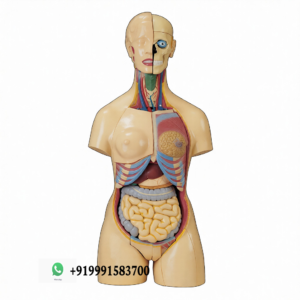

Related Products

Related products